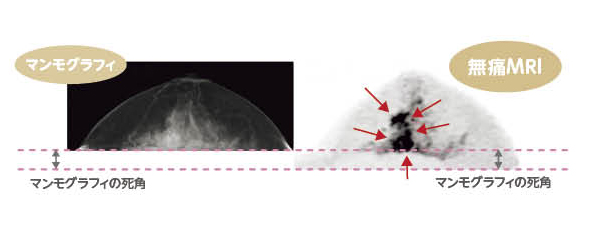

このMRIを用いた検診は圧迫しないので痛くもなく(図1)、専用の検査衣を着用するので恥ずかしさもありません。また、高濃度乳房でマンモグラフィでは見つかりにくい病変も検出しやすいとされています(図2)。乳がんの手術後などでインプラントが挿入されていても検査可能(一部除外品あり)です。

図2:日本人に多いとされる高濃度乳房の場合、マンモグラフィでは見つけにくい病変も、無痛MRI乳がん検診の場合は検出しやすいとされています。